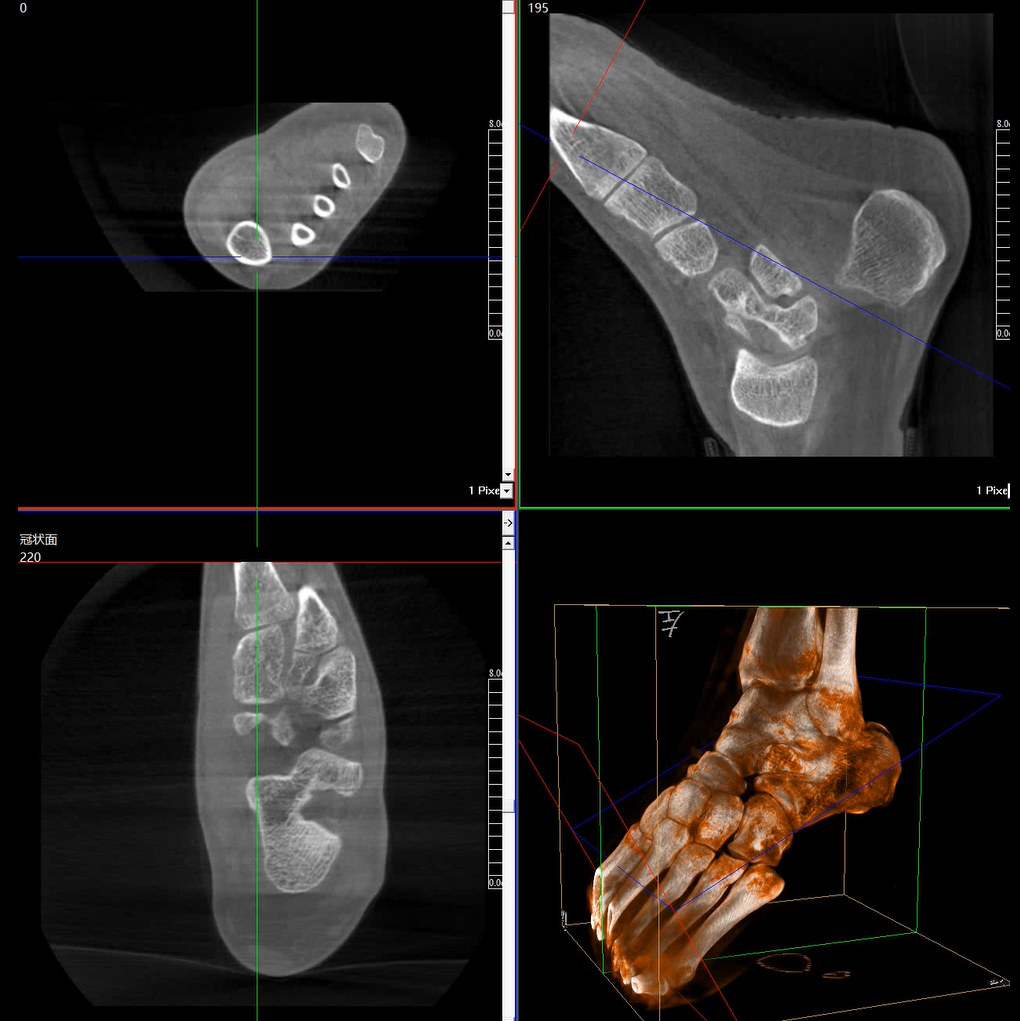

術中三維成像和橫斷面圖像提供多角度的手術診斷信息,輔助醫生進行術中評估判斷,諸如骨折復位情況和內植入螺釘的尺寸和位置,輔助手術更好地完成。

提供更大的術中三維成像視野,采集更多圖像信息,可一次拍全全段頸椎、全段腰椎、七節胸椎、雙側骶髂關節、股骨頭及單側盆骨。

在C臂掃描過程中,始終保持拍攝主體處于射線束的中心,避免了序列圖像采集過程中的橫縱方向運動,減少相對運動造成的運動偽影。